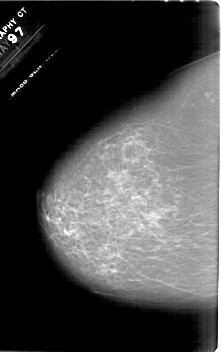

A_1618_1.LEFT_MLO

A_1618_1.LEFT_CC

LEFT_CC LINES 6676 PIXELS_PER_LINE 4186 BITS_PER_PIXEL 12 RESOLUTION 43.5 NON_OVERLAY

LEFT_MLO LINES 6031 PIXELS_PER_LINE 4321 BITS_PER_PIXEL 12 RESOLUTION 43.5 NON_OVERLAY